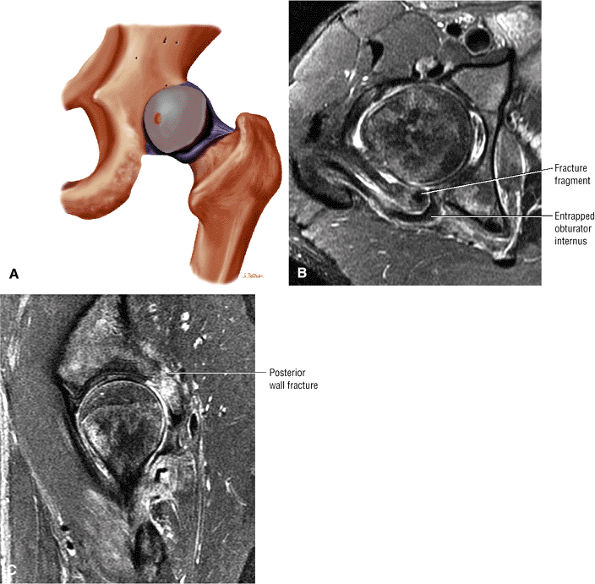

Femoral cysts with fluid, synovial/fibrous, or fat signal intensity (Fig. 3.188), which may be associated with reactive subchondral edema (Fig. 3.189)

-

A femoral head chondral crease (Fig. 3.190) in DDH with labral hypertrophy. The femoral head articular crease is medial to the dysplastic bump. The bump and crease are characteristically proximal to the physeal scar, in comparison to non-DDH cam impingement.